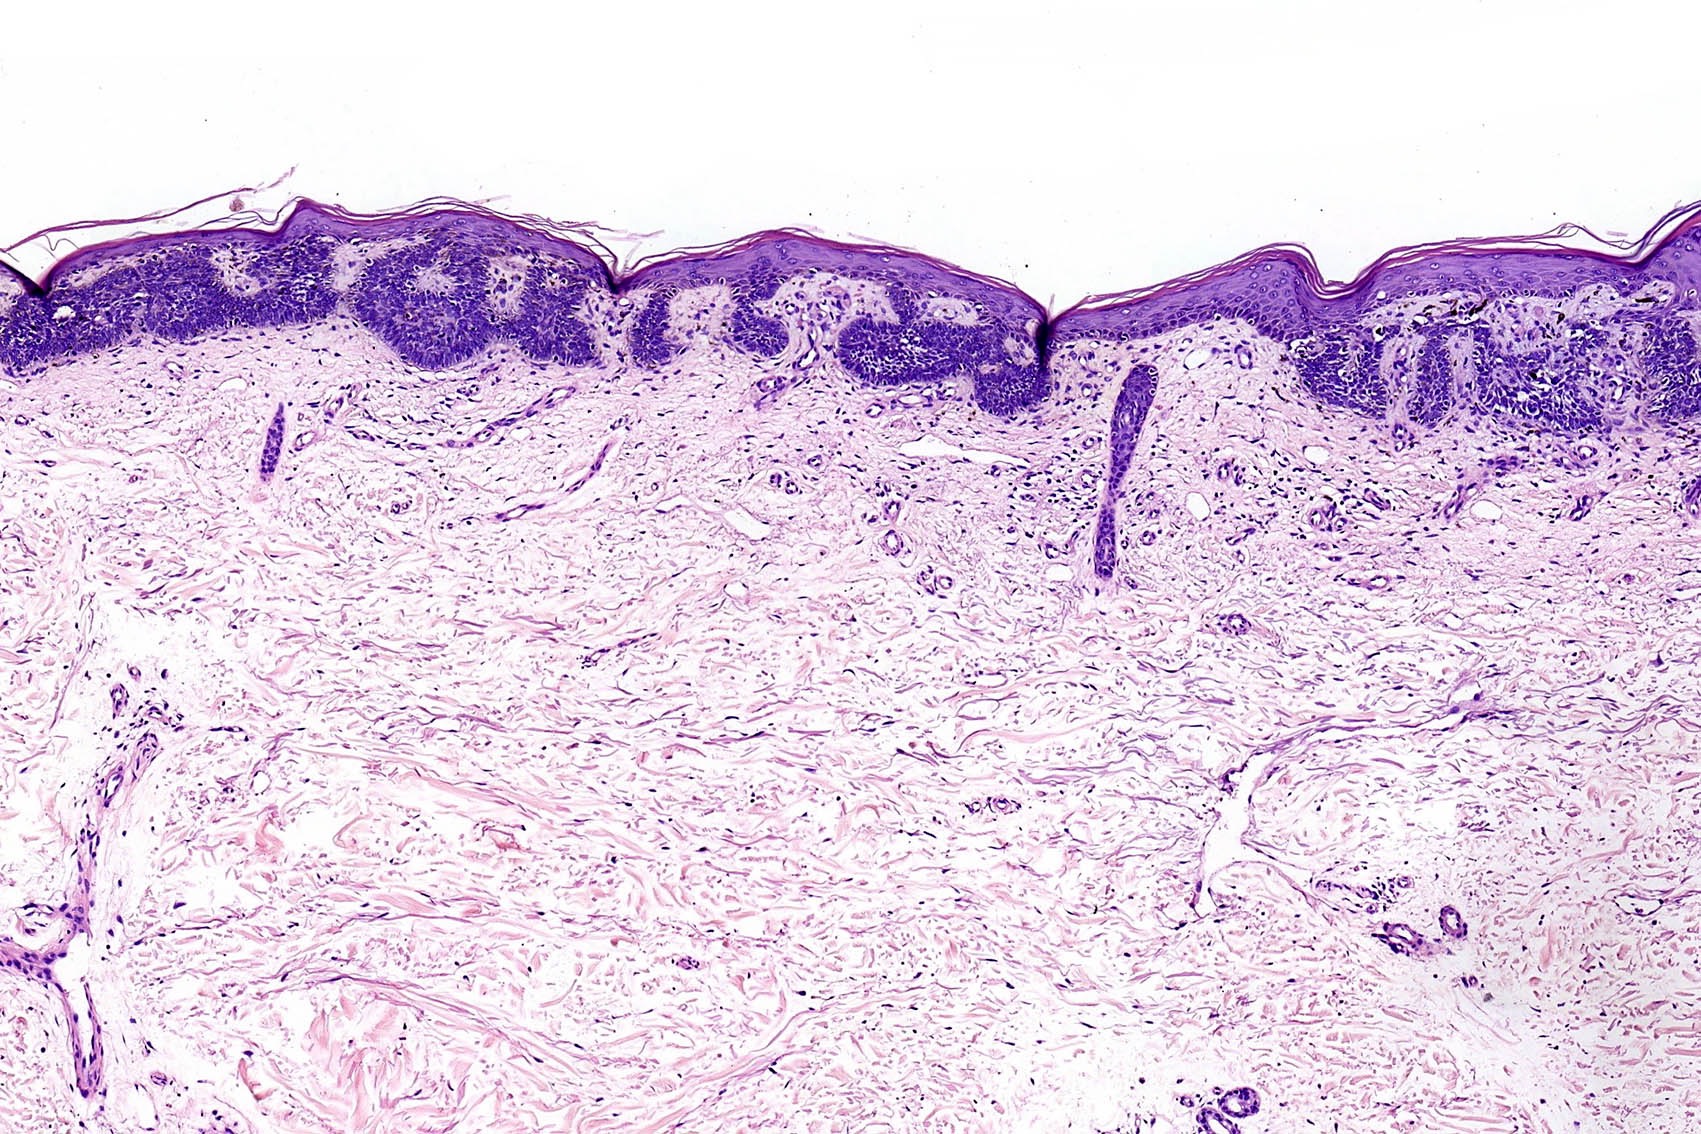

- Superficial BCC

- Isolated basaloid lobules projecting from the lower margin of the epidermis

Microscopic (histologic) images

Contributed by Antonina Kalmykova, M.D., Phillip H. McKee, M.D., Sate Hamza, M.D., Eduardo Calonje, M.D.,

Wayne Grayson, M.B.Ch.B., Ph.D., James Sampson, M.B.B.S., M.Sc. and Assia Bassarova, M.D., Ph.D.